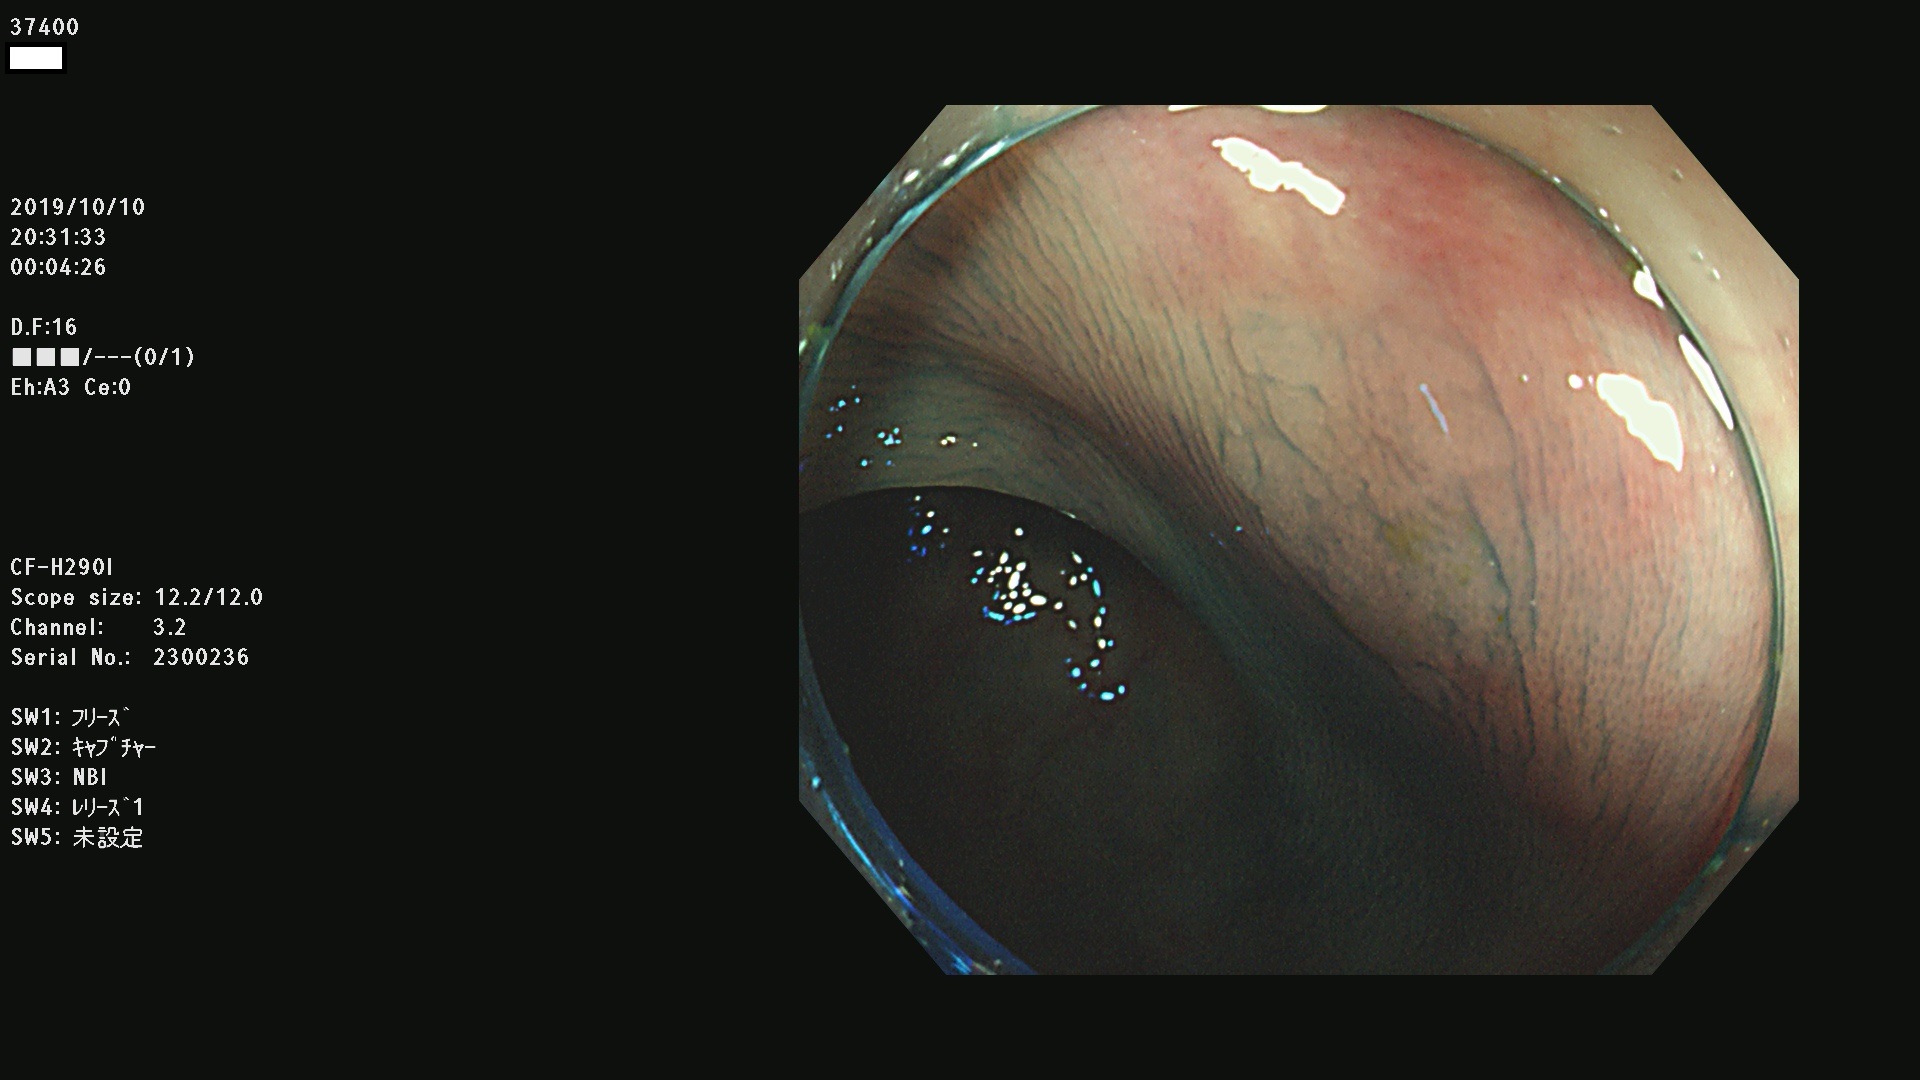

37400(SSAPのみ) 37401 37403 37404 37405 37406 37407 37408 37410 37411 37412 37413 37415 37416 37417 37420 37423 37424 37425 37426 37428 37430(SSAPのみ) 37432 37433 37434 37435 37436 37437 37438 37439 37440 37442 37443 37444 37447 37448 37449 37450 37451 37452 37455 37456 37457 37458 37459 37460 37461 37462 37464 37467 37468 37469 37470(SSAPのみ) 37471 37472 37474 37476(SSAPのみ) 37477 37478 37480 37481 37482 37483 37485 37486 37487 37488 37489 37490 37491 37492 37493 37494 37497 37499

発見困難で危険性の高い平坦型病変(上記100名より抽出)